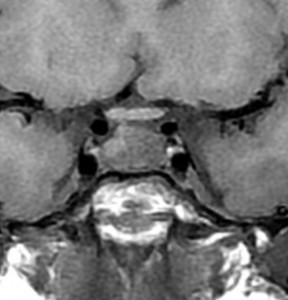

術後5ヶ月のMRIです,無理して全摘出しませんでしたので残存腫瘍のように見えます。病理診断では,出血,慢性炎症性細胞浸潤を伴い,コレステリン結晶やヘモジデリンの沈着,泡沫組織球,多核巨細胞浸潤を伴った繊維性組織片に,少量の上皮組織塊があり,少量の正常下垂体組織も付着していると報告されました。施設によってはこの所見をラトケのう胞と病理診断するかもしれません。

術後には軽度の尿崩症がでましたが,1年半でデスモプレッシンを中断できて,下垂体機能は正常化しました。

1年半を要して残存腫瘍は徐々に縮小しました。この画像は術後3年半のもので,正常下垂体がトルコ鞍右側に偏って見えます。